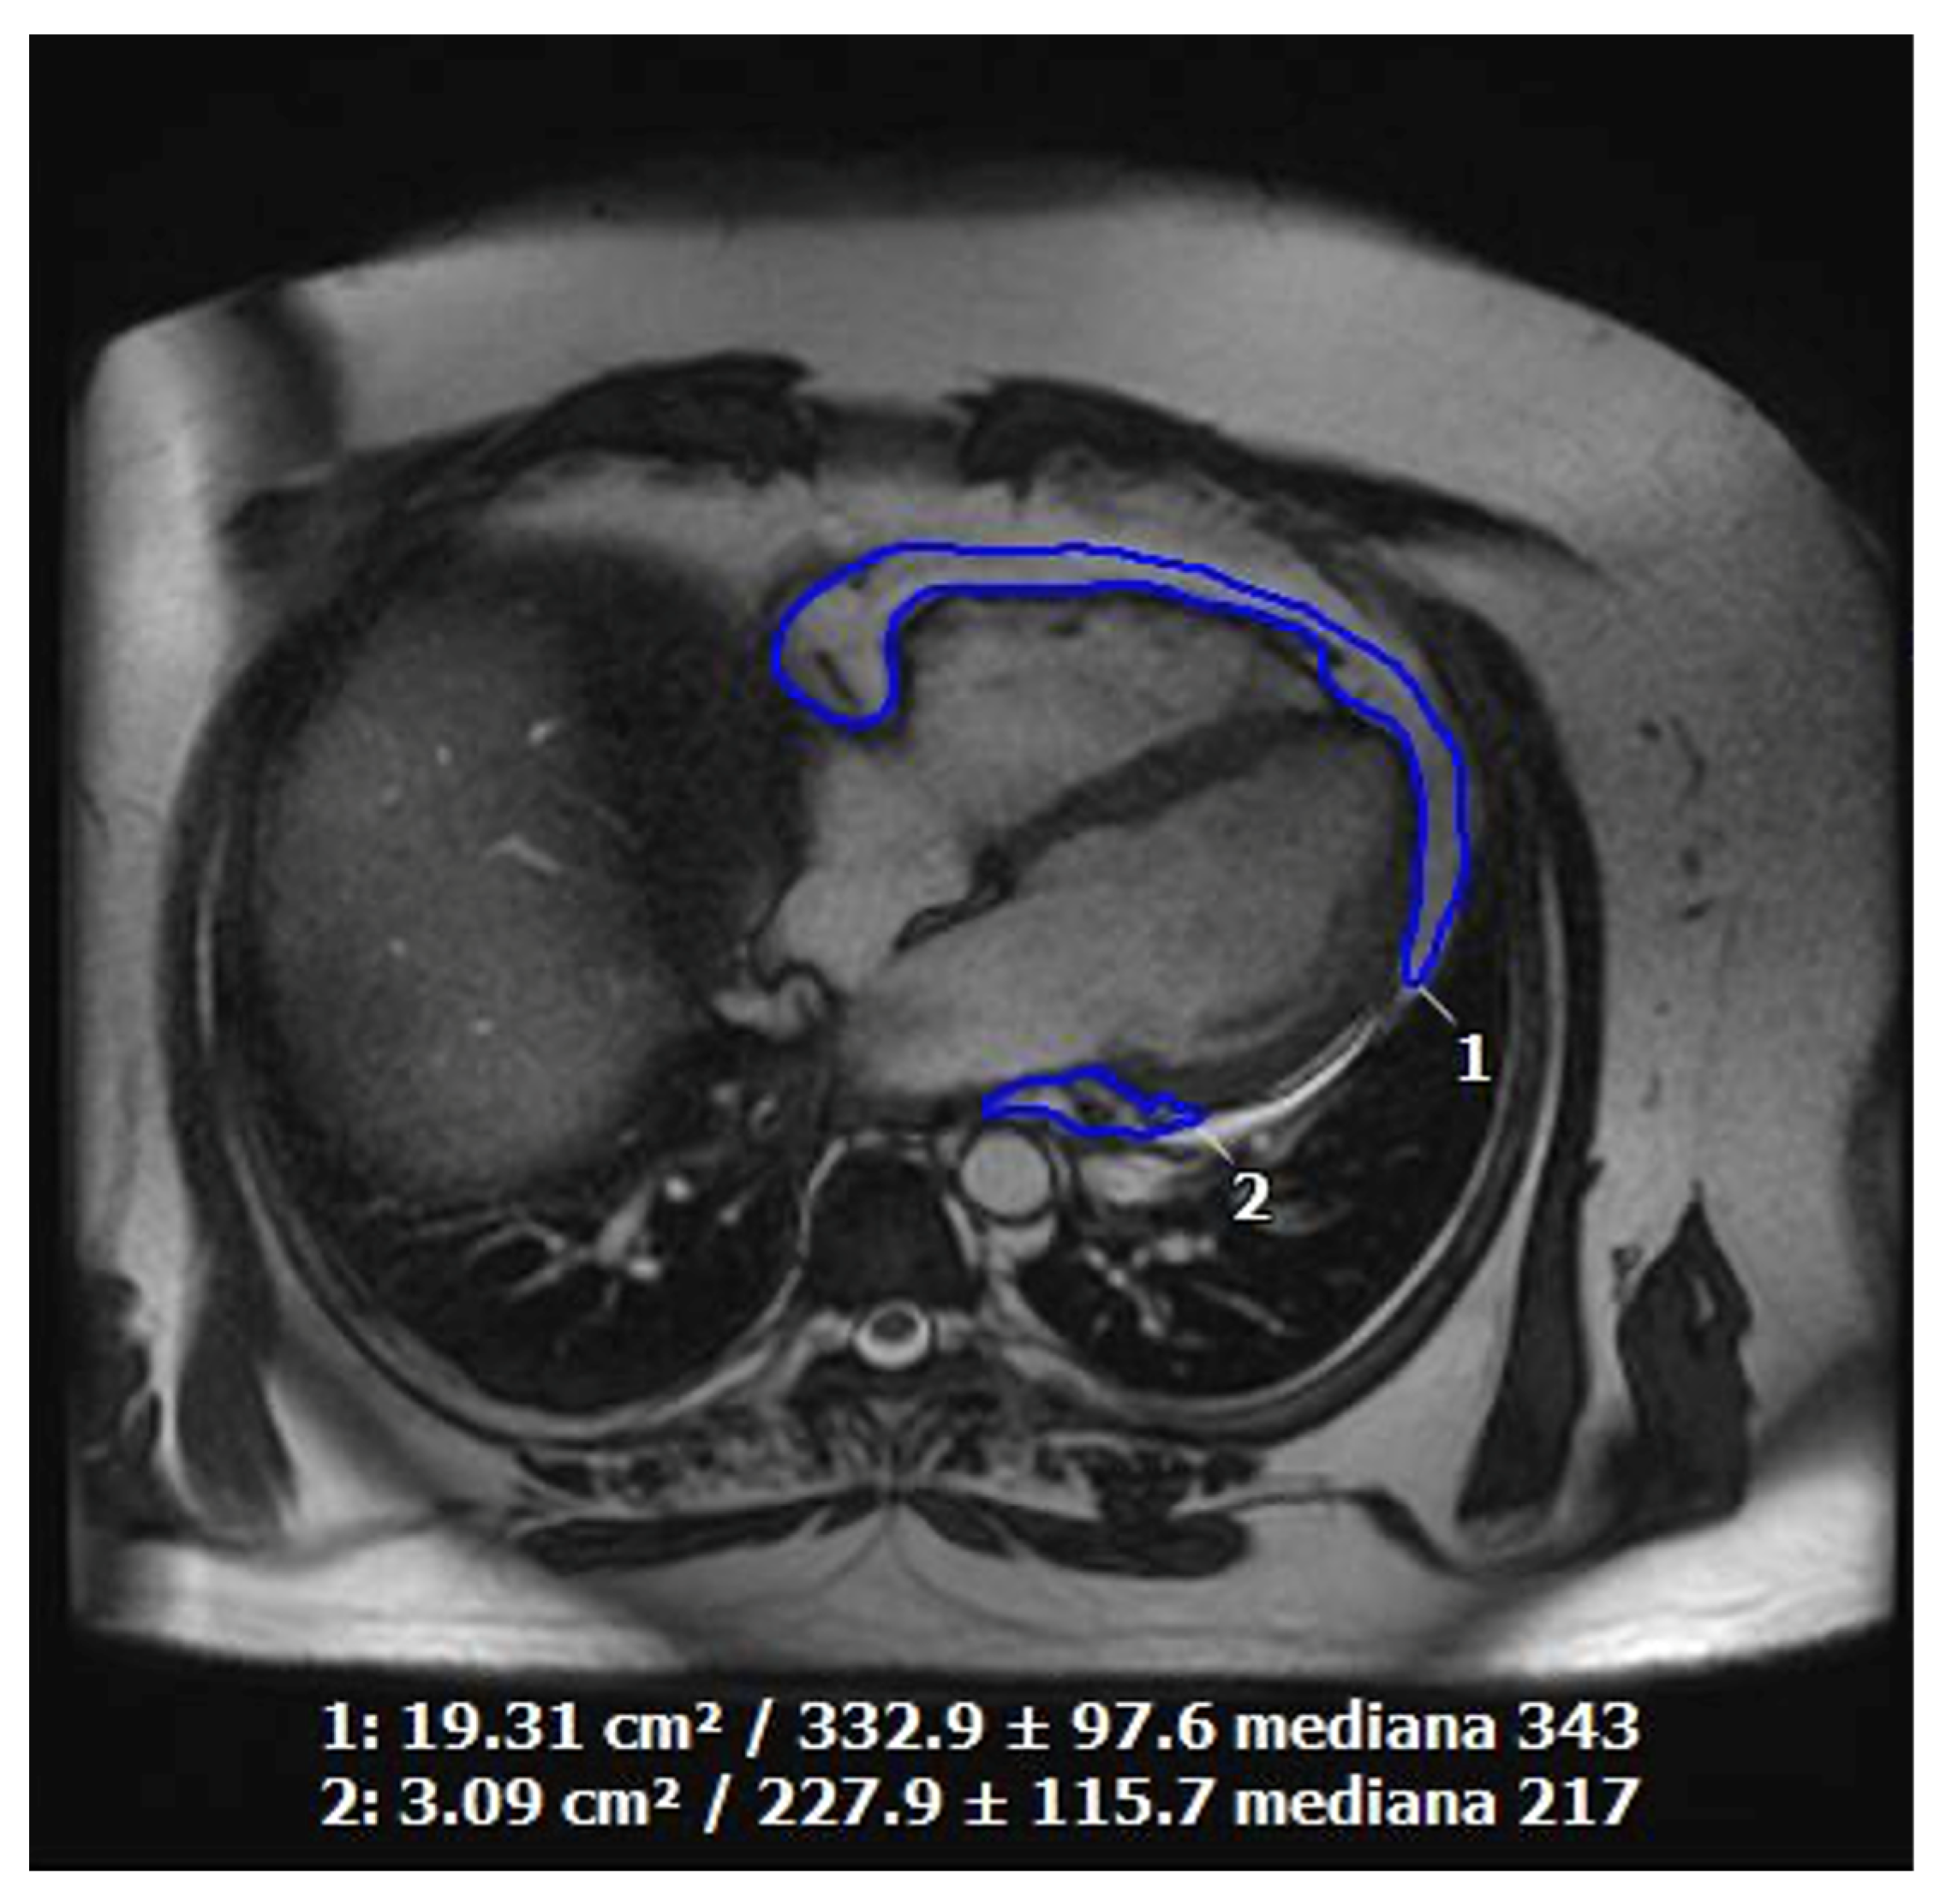

11. Cardiac Magnetic Resonance Imaging in Cardiovascular Prevention